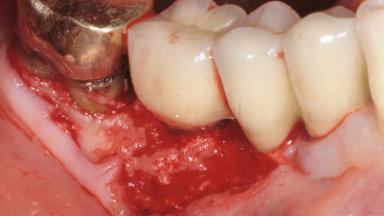

Surgical Management of Peri-Implantitis: Removal of Implant Due to Recurrent Infection Using an Implant-Retrieval Tool

Despite anti-infective surgical treatment, some patients may experience recurrent infection and progressive bone loss requiring additional treatment. This case describes a conservative approach using an implant retrieval tool without the need for excessive bone removal or use of a trephine.

A 65-year-old female patient was referred to the periodontist for assessment and management of infection associated with an implant at site 12. The general dentist had noted suppuration on probing during examination.